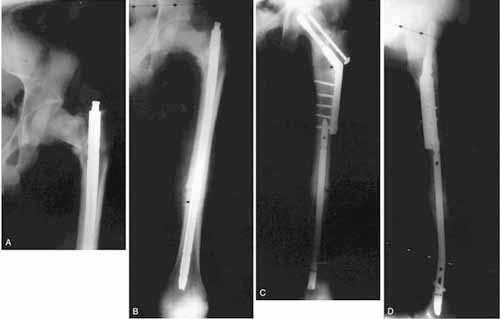

Fig 2A-D. Nonunion of the femoral neck and shaft is shown. (A) Varus nonunion with shortening of the femoral neck, resulting from early removal of proximal lag screws from the neck fracture for what was thought to represent hardware irritation is shown. (B) Radiograph shows varus nonunion in the proximal femur and a femoral shaft nonunion. (C) Radiograph taken at 4-year followup shows healed proximal femoral neck and shaft nonunions treated with a valgus intertrochanteric osteotomy and a reamed retrograde intramedullary nail. (D) Lateral view shows healing of the neck and shaft nonunion components.